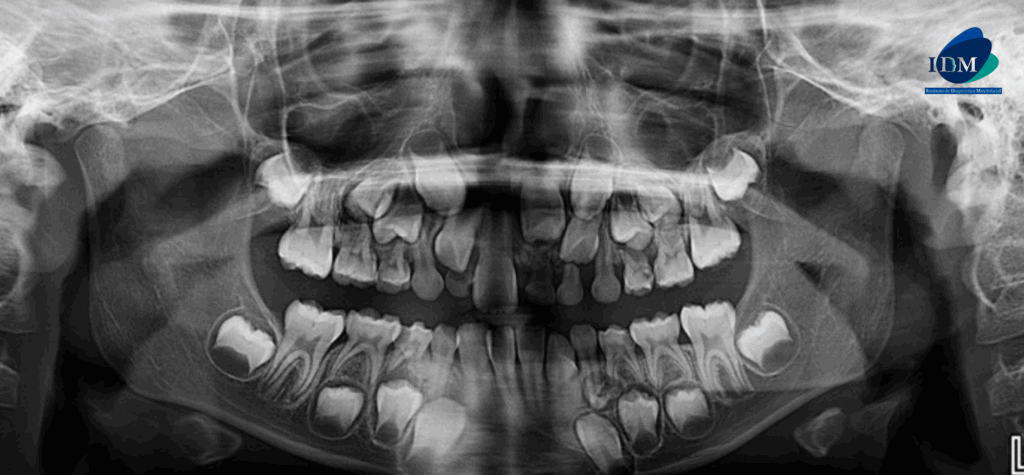

A la evaluación de la tomografía volumétrica (CBCT) en los cortes axiales (Figura 2) y transaxiales (Figura 3), se aprecia pieza supernumeraria en posición invertida localizada hacia palatino de pieza 21, segmento coronario mesial en contacto con la cortical de conducto nasopalatino. Asimismo, se observa imágenes hiperdensas circunscrita por un halo hipodenso localizado adyacente a cima del reborde alveolar a nivel de pieza 21, que ocasiona desplazamiento de pieza 21 hacia vestibular.

CORTES AXIALES